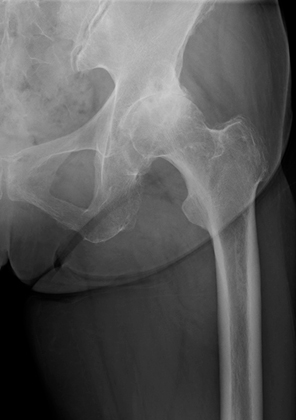

①変形性股関節症

何らかの原因で関節軟骨が摩耗して変性し、股関節が変形する疾患です。主な症状は、股関節の痛み、股関節の動きの制限、ひきずり足歩行(跛行)です。変形が進行すると、変形した側の脚(あし)の長さが短くなり、左右の脚の長さが違ってくることもあります。加齢や関節の使い過ぎなどによって起こる「一次性変形性股関節症」と、生まれつき寛骨臼のかぶりが浅いこと(臼蓋形成不全)が原因で起こる「二次性変形性股関節症」があります。欧米では一次性が大半を占めますが、日本では二次性が多いという特徴があります。寛骨臼のかぶりが浅いと、大腿骨頭を十分に覆うことができないため、関節軟骨の狭い範囲に負担が集中し、変形が進行しやすくなります。

![]() 術前レントゲン |